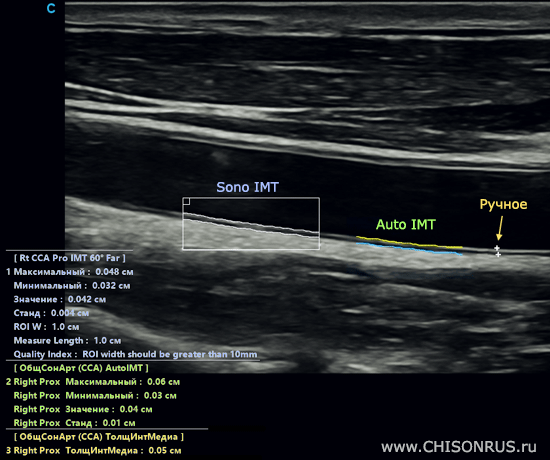

Пример измерений Sono IMT, Auto IMT и ручного измерения на одном кадре на общей сонной артерии:

SonoIMT измеряет стенку сосуда с повышенной точностью - с дополнительным знаком после запятой, а также автоматическое оконтуривание комплекса более аккуратное.